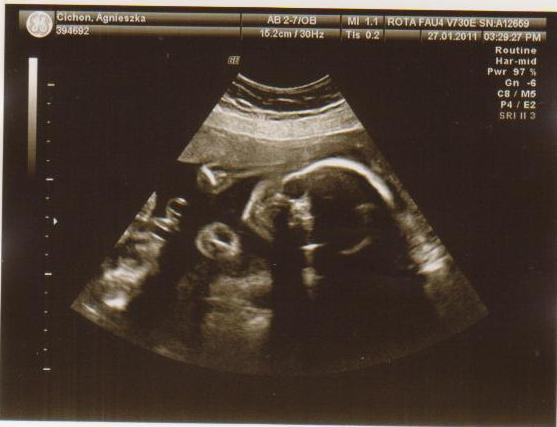

cześć dziewczyny to i ja chciałabym do Was dołączyć, właśnie znalazłam to forum. Mieszkam w Irlandii od 4 lat i mam synka 21 miesięcy, a teraz jestem w 28 tc bliźniaczej :-) dwie dziewczynki dwujajowe :-) też mnie trochę przeraża poród bliźniaków ale trzeba jakoś urodzić ;-) Pierwszy poród miałam jak marzenie szybko, sprawnie i nawet bez znieczulenia, mam nadzieję że i tym razem bęzie podobnie.

Hej podwojne mamunie:-)Ja juz rozpakowana dawno mamusia dubeltowka.Gratuluje wam serdecznie i witam w gronie tych wybranych hihiNiczego sie nie bojcie.Ciaxa blizniacza jest pod specjalna opieka.Czekaja was czeste wizyty w szpitalu i czeste ogladanie maluszkow na usg :-)